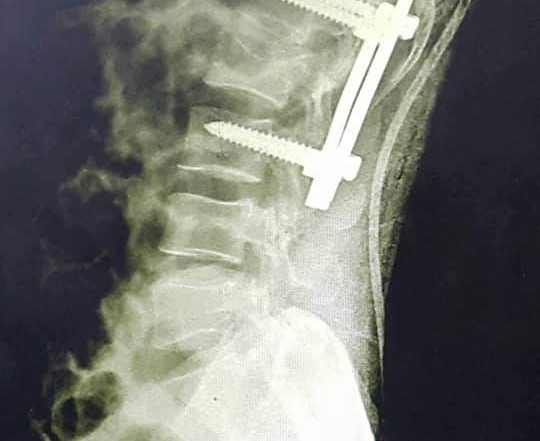

مستشفى الأوروبي ينقذ رجل خمسيني من شلل نصفي بتثبيت كسر في العمود الفقري

وفد ألمانى يغادر مستشفى الأوروبى بعد اجرائه لعمليات جراحية فى العمود الفقرى